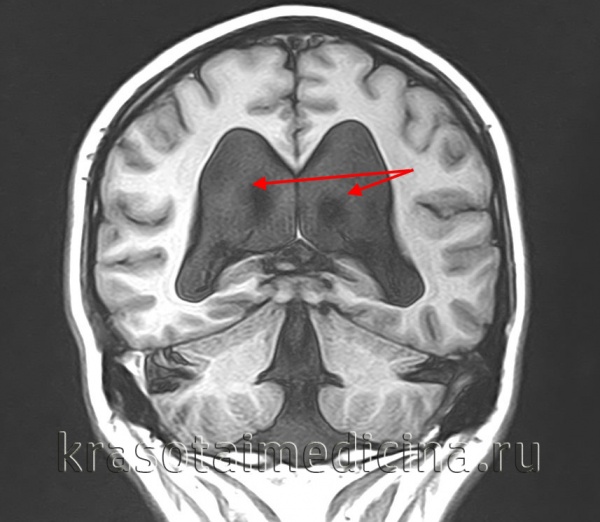

Добавлено: 26.04.2023, 03:30 Источник: ГидроцефалияГидроцефалия — повышенное скопление цереброспинальной жидкости в ликворной системе головного мозга. Гидроцефалия сопровождает многие врожденные и приобретенные неврологические заболевания. Клинически она проявляется признаками повышенного внутричерепного давления (головная боль, тошнота, давление на глаза), симптомами сдавления мозговых структур (вестибулярная атаксия, нарушения зрения, психические расстройства, эпи-приступы) и симптомами, характерными для вызвавшего ее заболевания. Диагностика гидроцефалии включает рентгенографию черепа, офтальмологические исследования, Эхо-ЭГ (у грудных детей — нейросонографию), МРТ или КТ головного мозга. Хирургическое лечение гидроцефалии позволяет скорректировать врожденные аномалии ликворной системы, провести удаление нарушающих ликвороциркуляцию внутричерепных образований, наладить отток ликвора из полости черепа. ![]() В головном мозге есть четыре желудочка – два боковых, а также так называемые третий и четвертый желудочки мозга. Из боковых желудочков ликвор поступает в третий желудочек, а оттуда – в водопровод мозга, или Сильвиев водопровод, через который жидкость поступает в четвертый желудочек. После этого спинномозговая жидкость вытекает в подпаутинное (субарахноидальное) пространство, окружающее головной и спинной мозг, где всасывается. ![]() Ликвор постоянно обновляется (вырабатывается около 500 мл ликвора в сутки) – вырабатывается и всасывается. Если баланс между выработкой спинномозговой жидкости и всасыванием нарушается, то есть ликвор вырабатывается быстрее, чем всасывается, то он начинает скапливаться внутри желудочков, они расширяются, а внутричерепное давление повышается. Такое состояние и называется гидроцефалией. Классификация гидроцефалииОсновная классификация предполагает выделение окклюзионной, или несообщающейся гидроцефалии (при закупорке ликворных путей), и сообщающейся гидроцефалии, когда нарушена всасываемость ликвора (встречается чаще), или вырабатывается слишком много ликвора при нормальном всасывании (встречается реже). Кроме того, гидроцефалия подразделяется: По локализации: внутренняя, когда увеличены желудочки мозга; наружная, когда увеличены субарахноидальные пространства; смешанная, когда увеличены и желудочки мозга, и субарахноидальные пространства. По стадии заболевания: компенсированная, когда расширение ликворных путей существует без клинических проявлений; субкомпенсированная, когда при расширенных ликворных путях присутствуют общемозговые симптомы; декомпенсированная, когда при расширенных ликворных путях присутствуют очаговые неврологические симптомы. По этиологии: врожденная гидроцефалия – развивается в результате перинатальных внутричерепных кровоизлияний, опухолей головного мозга, воспалительных процессов, после черепно-мозговой травмы, вследствие патологий сосудов головного мозга; приобретенная гидроцефалия – инфекционная, постгеморрагическая (после кровоизлияний), при объемных внутричерепных процессах, в результате гиперпродукции ликвора, например, при опухолях сосудистых сплетений, выстилающих желудочки мозга. Функциональная классификация: В зависимости от уровня ликворного давления различают: гипертензивную гидроцефалию (давление повышено); нормотензивную гидроцефалию (давление в норме). Некоторые классификации выделяют еще острую гидроцефалию (декомпенсация происходит в срок до 3 суток), подострую проградиентную (декомпенсация состояния происходит в течение месяца) и хроническую гидроцефалию. Следует помнить, что гидроцефалия – это развивающееся состояние, и скорость прогрессирования может изменяться с течением времени. Кроме того, острое начало может сменяться хроническим течением, в то время как хроническая гидроцефалия может сопровождаться обострениями, требующими смены тактики лечения. ДиагностикаКлинические симптомы гидроцефалии обычно настолько характерны, что позволяют неврологу заподозрить ее наличие при первом же осмотре пациента. Для определения степени и формы гидроцефалии, а также для выявления лежащего в ее основе заболевания проводятся дополнительные обследования: Рентген. При рентгенографии черепа выявляется истончение костей черепа и расхождение швов между ними; на внутренней поверхности свода черепа наблюдается симптом «пальцевых вдавлений». Гидроцефалия, обусловленная стенозом водопровода мозга, сопровождается уменьшением объема задней черепной ямки на рентгенограммах черепа. Гидроцефалия при синдроме Денди-Уокера, наоборот, характеризуется увеличением объема задней черепной ямки на краниограммах. Гидроцефалия при закрытии одного из межжелудочковых сообщений проявляется видимой на краниограмме асимметрией черепа. Компьютерная или МР-томография. Томографические методы диагностики дают возможность определить характер гидроцефалии, выявить место окклюзии ликворных путей или имеющуюся врожденную аномалию, диагностировать причинное заболевание (опухоль, киста, гематома и т. п.). При гидроцефалии наиболее информативно применение МРТ головного мозга. При подозрении на сосудистые нарушения показана МРА сосудов головного мозга. МРТ головного мозга. Выраженное расширение боковых желудочков окклюзионного характера. ![]() Эхография. Из методов УЗИ-диагностики при гидроцефалии применяется эхоэнцефалография, позволяющая определить степень повышения внутричерепного давления. У детей первого года жизни возможно УЗИ-сканирование головного мозга через открытый родничок при помощи ультрасонографии. Консультация офтальмолога. Оценку зрительных нарушений и состояния дисков зрительных нервов производит офтальмолог. Как правило, в перечень офтальмологических обследований при гидроцефалии входит офтальмоскопия, определение остроты зрения и периметрия. Люмбальная пункция . При отсутствии противопоказаний для выявления причинного заболевания возможно проведение люмбальной пункции с последующим исследованием цереброспинальной жидкости. Врожденная гидроцефалия инфекционной этиологии требует проведения ПЦР-диагностики для определения вида вызвавшей ее инфекции. Лечение гидроцефалииВыбор метода лечения гидроцефалии зависит от ее этиологии. Консервативная терапия часто проводится при приобретенной гидроцефалии, обусловленной воспалительными заболеваниями, перенесенной ЧМТ, кровоизлиянием в желудочки. Осуществляется лечение основного заболевания, а для уменьшения степени гидроцефалии и повышенного внутричерепного давления назначаются мочегонные препараты (ацетазоламид, фуросемид). Врожденная гидроцефалия обычно требует хирургического вмешательства, направленного на коррекцию лежащего в ее основе порока развития. Если гидроцефалия обусловлена наличием объемного процесса в головном мозге, то она также лечится хирургическим методом. По показаниям производится удаление внутричерепной гематомы, операции по удалению опухолей, вскрытие или тотальное иссечение абсцесса головного мозга, разъединение спаек при арахноидите и др. В случаях, когда устранить причину гидроцефалии не представляется возможным применяются шунтирующие операции: